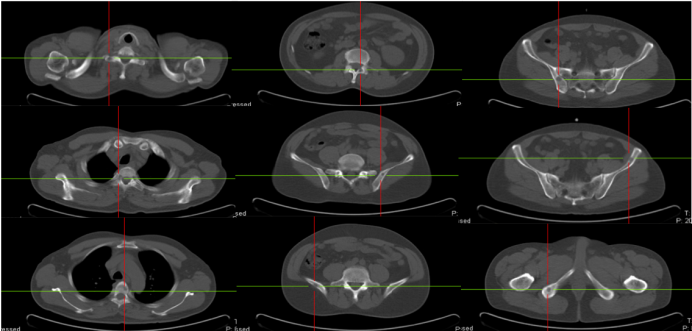

骨骼是肺癌常见的转移部位之一,骨转移癌会导致骨痛、病理性骨折、脊髓压迫、高钙血症等骨相关事件(SRE),其中,骨痛是骨转移癌最常见的临床症状,严重影响患者生活质量。地舒单抗,首个落户中国的核因子κB受体活化因子配体(RANKL)抑制剂,为防治SRE提供新的选择。本次分享地舒单抗治疗以骨痛为主要症状的EGFR突变晚期肺癌骨转移患者案例,希望为SRE的防治带来启迪与思考。 白引苗 空军军医大学第一附属医院肿瘤科 主治医师 中国抗癌协会肿瘤标志物专业委员会 委员 陕西省抗癌协会肿瘤化疗专业委员会 委员 陕西省抗癌协会肿瘤热疗专业委员会 委员 陕西省抗癌协会多原发和不明原发肿瘤专业委员会委员 擅长食管癌、胃癌、结直肠癌、胰腺癌等消化系统、肺癌及妇科常见恶性肿瘤的化疗、靶向治疗及免疫治疗等内科治疗。参译著作1部,参编著作1部,发表核心期刊论文多篇。 一般资料:患者男性,60岁 主诉:右侧肩部疼痛 现病史:2019年8月因右侧肩部疼痛于外院就诊,疼痛NRS评分3-4分,口服依托考昔症状可缓解 个人史:否认吸烟、饮酒嗜好 家族史:1兄因“胃癌”病故 辅助检查: 外院右肱骨MRI:右侧肱骨骨转移可能,合并肱骨中段骨质破坏。 外院胸部CT(图1):右肺下叶周围型肺癌,可疑肺门、纵隔淋巴结转移,T3/4/8椎体骨转移。 图1 胸部CT(箭头指示右肺下叶病变) PET/CT(18F-FDG)(图2-3):右肺下叶基底段软组织病变(3.7 cm×4.6 cm×4.7 cm,SUV max 6.9,平均值6),浅分叶、边缘见毛刺;右侧锁骨上下区、隆突区稍大淋巴结(长径0.6 cm-1.4 cm,SUV max 2.5-4.6,平均值2.2-3.2),考虑转移;脊柱多个椎体及附件、双侧多个肋骨、骨盆多处、双侧股骨上段多发骨质破坏(SUV max 2.0-5.7,平均值1.7-3.9),考虑转移。 图2 PET/CT提示右肺下叶基底段病变及右锁骨上下区、隆突区稍大淋巴结 图3 PET/CT提示多发骨质破坏 患者接受CT引导下经皮右肺病变穿刺活检,病理(图4):光镜见异型细胞呈条索状、腺管样排列,细胞核大、深染,异型性明显;免疫组化:AE1/AE3(+),CK5/6(-),CK7(+),CK8/18(+),P40(-),P63(-), Napsin A(+),ALK(D5F3 Ventana IHC)(-),TTF-1(+),Ki67 30%,支持腺癌。 肿瘤标志物:CYFRA21-1 5.8 ng/ml(参考值:0-3.3 ng/ml),CEA、SCC、NSE正常。 基因检测:EGFR基因19del突变。KRAS、NRAS、PIK3CA、BRAF、HER-2基因未检测到突变;ALK、ROS1、RET基因未检测到融合。 诊断:肺恶性肿瘤(右侧,腺癌,cT2N3M1,IV期,EGFR 19del);骨继发恶性肿瘤(多发);淋巴结继发恶性肿瘤(多发)。 双管齐下、并驾齐驱——抗癌治疗与唑来膦酸齐头并进 2019年9月患者接受奥希替尼80 mg/日一线治疗,同时接受唑来膦酸4 mg/月改善SRE。1个月后复查CT示右肺病变缩小40%(4.7 cm至2.8 cm);肿瘤标志物CYFRA21-1由5.8 ng/ml降至3.67 ng/ml;右肩部疼痛消失(停用止痛药)。 2020年3月复查胸部CT(图5)提示:肺部病变进展(增大39.3%,2.8 cm至3.9 cm);肿瘤标志物CYFRA21-1缓慢升高至7.05 ng/ml。考虑局部进展,在奥希替尼基础上联合培美曲塞+卡铂治疗4个周期,后给予奥希替尼联合培美曲塞维持治疗14个周期。 图5 胸部CT(2020年3月,箭头指示右肺病变) 最佳疗效:右肺病变缩小51.3%(至1.9 cm)(图6);肿瘤标志物CYFRA21-1由7.05 ng/ml降至1.4 ng/ml。 图6 二线治疗前(左图)后(右图)胸部CT比较(箭头指示右肺病变) 2021年4月患者感背部钝痛,NRS评分5-6分,口服氨酚羟考酮330 mg/8 h,症状可缓解。骨扫描(ECT)与单光子发射计算机断层扫描(SPECT)/CT提示骨转移加重。停用唑来膦酸,使用地舒单抗120 mg/月,疼痛有缓解。 2021年9月复查胸部CT示右肺下叶病变进展(1.9 cm至3.4 cm)。肿瘤标志物CYFRA21-1由10.73 ng/ml升至13 ng/ml。患者感背部疼痛加重,NRS 评分5-6分。行CT引导下右肺病变再次穿刺活检,病理提示肺腺癌,PD-L1(SP263)(TPS=80%),Ki67 85%。基因检测:EGFR 19del,KRAS、NRAS、PIK3CA、BRAF、HER-2基因及MET exon14无突变;ALK、ROS1、RET基因无融合。 遂调整为白蛋白结合型紫杉醇化疗2周期,奥希替尼和地舒单抗方案同前,患者背部疼痛消失。 2021年11月复查PET/CT:原右肺下叶基底段团块状软组织病变较初诊缩小(1.8 cm×1.6 cm×3.8 cm);原右侧锁骨区多发淋巴结消失;原隆突区稍大淋巴结缩小(0.5 cm);原脊柱多个椎体及附件、双侧多个肋骨、骨盆多处、双侧股骨上段多发骨质破坏,病变密度增高,考虑治疗有效,部分仍有代谢活跃;右侧颞叶片状低密度影。查头颅MRI(图7):左侧额叶大脑镰旁(0.7 cm×0.7 cm×1 cm)、右侧颞叶脑皮质表面(1.2 cm×1.3 cm×0.8 cm)异常强化灶,考虑转移。 图7 头颅MRI(箭头指示颅内病变) 经MDT讨论,建议脑部病变随诊观察。鉴于出现脑转移癌,调整为伏美替尼80 mg/日口服、白蛋白结合型紫杉醇静脉化疗;继续予地舒单抗。 患者治疗期间碱性磷酸酶(ALP)水平变化如图8所示。 图8 血清碱性磷酸酶变化情况 患者于2019年8月因右侧肩部疼痛就诊,确诊右肺腺癌Ⅳ期伴多发骨转移及淋巴结转移,EGFR 19del突变。一线治疗:奥希替尼(80 mg/日)+骨改良药物唑来膦酸(4 mg/月),最佳疗效:右肺肿瘤PR(缩小40%)、疼痛症状缓解,一线治疗PFS时间7个月。2020年3月,肺部病灶进展,予奥希替尼+培美曲塞联合卡铂4周期,后培美曲塞维持治疗14周期,继续予唑来膦酸治疗;2021年4月背部钝痛加重,骨扫描提示骨病变进展,遂停用唑来膦酸,予地舒单抗120 mg/月治疗至2021年9月,二线PFS 18个月。后因肺部病灶进展,三线治疗给予奥希替尼+白蛋白结合型紫杉醇及地舒单抗,患者背部疼痛症状消失。2021年11月头颅MRI示颅内转移,调整为予伏美替尼(80 mg/日)联合白蛋白结合型紫杉醇及地舒单抗治疗。 张红梅 西京医院肿瘤科主任 肿瘤学博士,硕士研究生导师 中国抗癌协会CMUP 副主委 中国临床肿瘤学会免疫专家委员会 常委 陕西省医学会肿瘤内科分会 副主委 主要从事肺癌等恶性肿瘤的内科治疗 我国肺癌发病率和死亡率均位于恶性肿瘤首位,20%-30%的晚期肺癌会发生骨转移[1],45%的肺癌骨转移患者会出现相关临床症状[2]。肺癌骨转移是患者生活质量降低、生存期缩短的独立危险因素,SRE如骨痛、病理性骨折、脊髓压迫等,不仅给患者带来生理上的痛苦与不便,也引发患者心理打击。因此,对于晚期肺癌骨转移患者,在控制原发疾病同时,亟需积极防治SRE,以达到提高患者生活质量、缓解生理心理痛苦、延长生存期的目的[3]。 本例肺癌同时性骨转移案例,以骨痛为首发症状,在奥希替尼治疗肺癌同时,首先予以唑来膦酸防治SRE,治疗初期患者症状一度改善。但随着疾病进展,唑来膦酸应用近20月后患者再次骨痛加重,影像学提示骨损害加重,对于这种骨病变进展、骨痛加重的临床问题,如何制定进一步治疗方案? 地舒单抗是IgG2型单克隆抗体,通过与RANKL结合,阻止其激活破骨细胞、破骨细胞前体和破骨细胞样巨细胞表面的核因子-κB受体活化因子(RANK),从而达到抑制肿瘤生长、减少骨破坏的目的。早在2010年,地舒单抗获得美国食品药品监督管理局(FDA)批准用于治疗实体瘤骨转移,目前已积累了丰富的证据临床研究和真实世界数据,显示其有效性和安全性。 地舒单抗与唑来膦酸治疗实体瘤骨转移和多发性骨髓瘤的Ⅲ期临床研究显示,地舒单抗可延缓首次出现SRE的时间(21.4个月 VS. 15.4个月)[4]。其中非小细胞肺癌患者,地舒单抗组较唑来膦酸组中位生存期(OS)延长1.5个月(9.5个月 VS. 8.0个月)[5]。安全性方面,地舒单抗也具有一定的优越性:与唑来膦酸组比较,地舒单抗组贫血、厌食症、肾脏不良事件、新发原发性恶性肿瘤的发生率较低[6]。地舒单抗通过网状内皮系统清除,不增加肾脏负担,对于肾功能不全的患者可作为首选。此外,作为皮下注射制剂,28天用药一次,无需住院完成,无疑为口服靶向药的肺癌骨转移患者带来极大的便利。 本例患者经唑来膦酸治疗后再次出现SRE,改用地舒单抗治疗至今,患者骨痛症状缓解,随访血清ALP水平逐渐下降,且耐受性良好。对这位长期与肺癌抗争的晚期患者,地舒单抗减轻了身体的疼痛,带来心灵的慰藉,实现临床获益。 2020年11月20日,地舒单抗在中国获得国家药品监督管理局(NMPA)批准,用于预防实体瘤骨转移及多发性骨髓瘤引起的SRE,随着药物可及性的进一步提高,期待地舒单抗可造福更多饱受骨转移折磨的中国肿瘤患者。 参考文献 1、Her nandez R K , Wade S W, Ly man GH, et al. I ncidence of bone metastases in patients with solid tumors: analysis of oncology electronic medical records in the United States. BMC Cancer, 2018, 18(1): 44. 2、Tsuya A, Kurata T, Tamura K, et al. Skeletal metastases in non-small cell lung cancer: a retrospective study. Lung Cancer, 2007, 57(2): 229-232. 3、北京医学奖励基金会肺癌青年专家委员会,中国胸外科肺癌联盟. 肺癌骨转移诊疗专家共识(2019版)[J]. 中国肺癌杂志, 2019, 22(4): 187-207. 4、Henry D, Vadhan-Raj S, Hirsh V, et al. Delaying skeletal-related events in a randomized phase 3 study of Denosumab versus zoledronic acid in patients with advanced cancer: an analysis of data from patients with solid tumors. Support Care Cancer. 2014 Mar; 22(3): 679-687. 5、Scagliotti GV, Hirsh V, Siena S, et al. Overall survival improvement in patients with lung cancer and bone metastases treated with Denosumab versus zoledronic acid: subgroup analysis from a randomized phase 3 study. J Thorac Oncol. 2012 Dec; 7(12): 1823-1829. 6、Fengxia Chen, Feifei Pu. Safety of Denosumab Versus Zoledronic Acid in Patients with Bone Metastases: A Meta-Analysis of Randomized Controlled Trials. Oncol Res Treat. 2016;39(7-8):453-459.基本情况